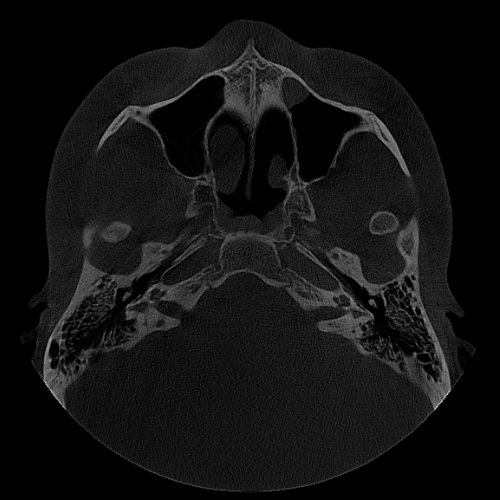

Patient Motion Correction (PMC)

The PreXion Excelsior MID algorithm automatically corrects the image imperfections caused by patient micro-movements. This ensures high exam quality, avoiding repetitions and offering greater accuracy for making diagnoses.